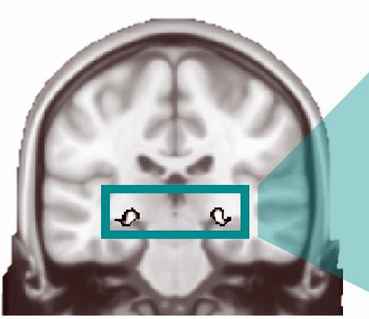

Dresden, 14. November 2024. Ein Teil der Probleme, den viele Autisten beim sozialen Kontakt mit anderen Menschen haben, könnte womöglich mit einer nur pfefferkorn-kleinen Struktur in ihrem Gehirn zu tun haben. Das hat ein Team um Neurowissenschaftlerin Katharina von Kriegstein von der TU Dresden ermittelt. Demnach ist dieser „magnozelluläre laterale Kniehöcker“ (mLGN) im Gehirn von Autisten weniger aktiv als bei anderen Menschen. Dies kann möglicherweise dazu führen, dass sie beispielsweise bei Gesprächen die Mimik ihres Gegenübers kaum zu deuten vermögen.

Der „magnozelluläre laterale Kniehöcker“ im Gehirn wiederum transportiere wichtige Sehinformation vom Auge zu der Großhirnrinde. Diese Struktur ist unter anderem auf die Wahrnehmung von Bewegungen spezialisiert, darunter Gesichtsbewegungen beim Lachen oder Sprechen. Allerdings ist dieser Gehirnteil winzig – „vergleichbar mit der Größe eines Pfefferkorns“, betont die Forscherin. Zudem liegt er tief im Gehirn, was die Untersuchung technisch herausfordernd macht. „In unserer Studie konnten wir die technischen Herausforderungen überwinden und liefern erstmals direkte Hinweise für Unterschiede in der Funktion des mLGN bei Autismus“, berichtet Stefanie Schelinski. Dabei untersuchte das Team die Sauerstoff-Sättigung im Blut ausgewählter Hirnregionen. „Damit eröffnen sich neue Perspektiven für die Autismus-Forschung, aber auch in anderen Forschungsbereichen, wie beispielsweise Schizophrenie und Legasthenie, die mit ähnlichen Wahrnehmungsbesonderheiten einhergehen können.“